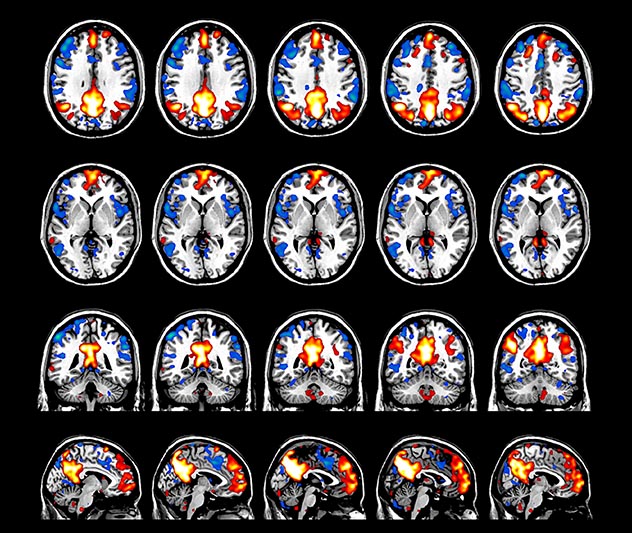

BOLD fMRI activation, depicted in color, of left anterior insula (MNI plane z = 8 mm) in a single subject by a contrast between viewing and matching faces with negative emotion (angry, sad, scared) versus happy faces. The voxelwise threshold is p < 0.001, and colored voxels survive false discovery rate correction to p < 0.05. The activated voxels in color are overlaid on the subject's own 3D-TFE image displayed in grayscale, after transforming the data to MNI space. The fMRI pulse sequence was a single shot FFE echo planar acquisition using MultiBand SENSE factor 6, dS SENSE factor 1, isotropic voxel size 2.4 mm, 60 transverse slices, TR 950 ms, TE 30 ms, flip angle 52 degrees, 517 dynamic scans, total scan duration 8:21 minutes. Image provided by James M. Bjork, PhD, Associate Professor of Psychiatry at VCU.

Imaging was performed using Ingenia 3T CX with a 32ch dS Head coil, TR 1.6 sec, TE 35 ms, voxel size 3.1 x 3.1 x 3.1 mm, 46 slices and Multiband SENSE factor 2. Image provided by Dr. Gispert

Default mode network as discovered by resting state fMRI in one participant of the ALFA cohort [7]. rs-fMRI allows us to find networks of brain regions with highly correlated activity and sustaining distinct brain functions. The default mode network (in warm color scale) is active when the brain is focused on introspective thinking and has been shown to be altered in Alzheimer’s. Interestingly, brain areas of this network are known to show abnormal levels of one of the pathological hallmarks of Alzheimer’s (b-amyloid deposition) in preclinical stages. We want to better understand the alterations of these brain networks in preclinical stages of Alzheimer's and explore their potential use as biomarkers.

The fMRI pulse sequence was a single shot FFE echo planar acquisition using MultiBand SENSE factor 5, dS SENSE factor 1.25, isotropic voxel size 2.7 mm, 50 transverse slices, TR 700 ms, TE 30 ms, flip angle 52 degrees, 765 dynamic scans, total scan duration 9:01 minutes. Image provided by Matthan Caan, PhD, Assistant Professor at the AMC.

Emotional n-back task combines a test of working memory with the use of emotive (faces) and neutral (places) images. The contrast in the images is between the activity when faces are presented compared to places, showing activation in the amygdala, fusiform, and occipital face areas.

Processing based on the Human Connectome Project (HCP) pipelines. The high resolution of the fMRI data allows extraction of the cortical surface, with minimal averaging of non-cortical signal. Surface based analysis provides improved cross-subject alignment, and prevents signal contamination between adjacent sulci.

Group analysis of 88 9- and 10-year olds part of ABCD, all scanned at UVM on Philips Achieva 3.0T dStream. Scale runs from red p=0.001 to yellow p<10ˆ-5. Images provided by Dr. Watts.

Acquisition using the ABCD protocol for fMRI with TR 800 ms, TE 30 ms, flip angle 52°, 2.4 mm isotropic imaging resolution with a 216×216×144 mm3 field of view using a MultiBand acceleration factor of 6 (60 slices, no gap). Two runs of 5 minutes per subject.